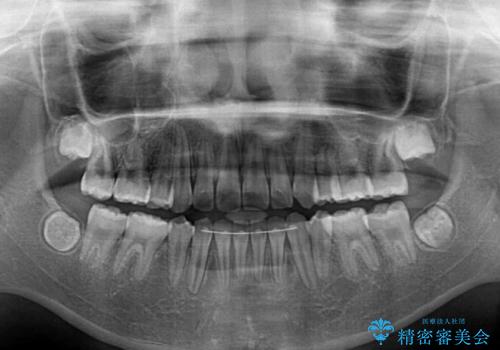

- 八重歯と乳歯が残っていることを気にして来院された患者様です。

乳歯が3歯残っており、下顎は左右ともに後続永久歯がない状態でした。

口元が突出しており、口が閉じにくかったため、乳歯を含め上下5歯を抜歯して矯正治療を行うこととしました。